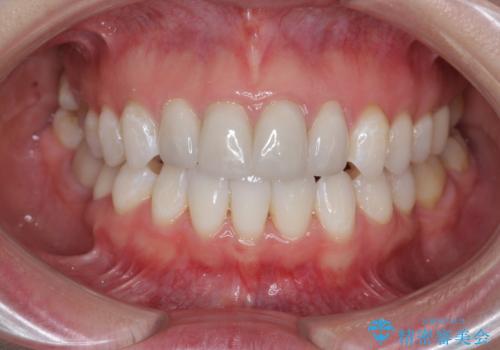

仮歯のまま放置していた前歯をセラミックに

- 仮歯のまま放置してしまい、変色を改善しきれいなセラミッククラウンをいれたい、と希望され来院されました。

特に虫歯の再発や神経の症状等問題を認めなかったので、審美的に優れるセラミッククラウンに仮歯を置き換えていきます。

- 52.8万円(ジルコニアクラウン×4・仮歯×4)費用は治療当時の料金となります

セラミッククラウンは長期的に変色しづらく、汚れのつきにくい審美製を長期的に保つことのできる治療方法です。